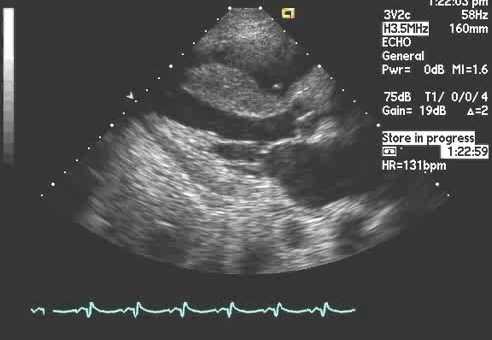

В современной медицине оценка систолической функции миокарда левого желудочка традиционно проводится в основном с помощью эхокардиографии, при этом применяется показатель механической систолы желудочков - фракция выброса (ФВ) левого желудочка [8, 9]. Однако эхокардиография имеет свои ограничения в виде отсутствия широкой доступности для всего населения, зависимости от профессионализма специалиста, расположения электродов, что влияет на точность измерения. Также существует сложность измерения ФВ в условиях тахикардии, что затрудняет точную оценку динамики систолической функции миокарда левого желудочка. Поэтому актуальными являются поиск и обоснование оценки систолической функции миокарда левого желудочка с помощью показателей электрической систолы, регистрируемой на ЭКГ, которая лишена приведенных выше недостатков эхокардиографии.

Учитывая, что в 40-49 % случаев у лиц с клиническими проявлениями сердечной недостаточности регистрируются нормальные показатели ФВ [10, 11], необходим дополнительный показатель, который позволял бы не только регистрировать состоявшуюся сердечную недостаточность, но и оперативно отслеживать динамику этой функции миокарда в процессе течения и лечения болезни. Целью настоящего исследования являлась необходимость обоснования дополнительного критерия в изучении систолической функции миокарда левого желудочка с помощью электрокардиографии, имеющей широкую доступность и простоту использования, высокую достоверность результатов и лишенной субъективного влияния на измерение при любой ЧСС.

В исследование были включены результаты обследования людей различного возраста (от 4 до 78 лет), которым были выполнены эхокардиография и электрокардиография. Для исследования были отобраны 140 человек, которые были разделены на две группы, состоящие из лиц с нормальными показателями ФВ (УЗИ) и электрической систолы желудочков Q-T (ЭКГ) в количестве 100 человек и лиц с нарушением ФВ и Q-T в количестве 40 человек.

В процессе исследования, используя УЗИ сердца и ЭКГ, определяли фазу выброса левого желудочка (ФВ по Симпсону), фазу изгнания (ФИ) в ЭКГ, фазу плато (ФП) в потенциале действия (ПД) с проекцией на ЭКГ и проводили их анализ на совпадение получаемых результатов в оценке систолической функции желудочков сердца.